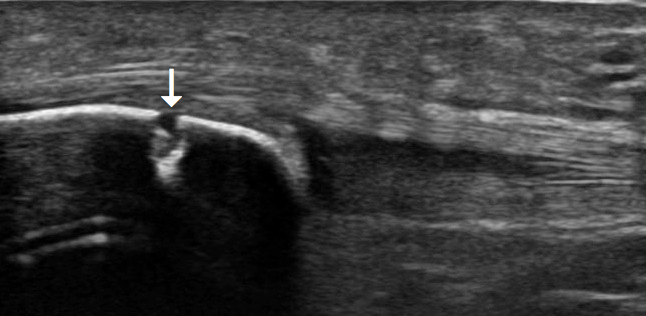

膝蓋骨疲労骨折の超音波像

膝蓋骨遠位部に骨皮質の途絶(矢印)が観察される。